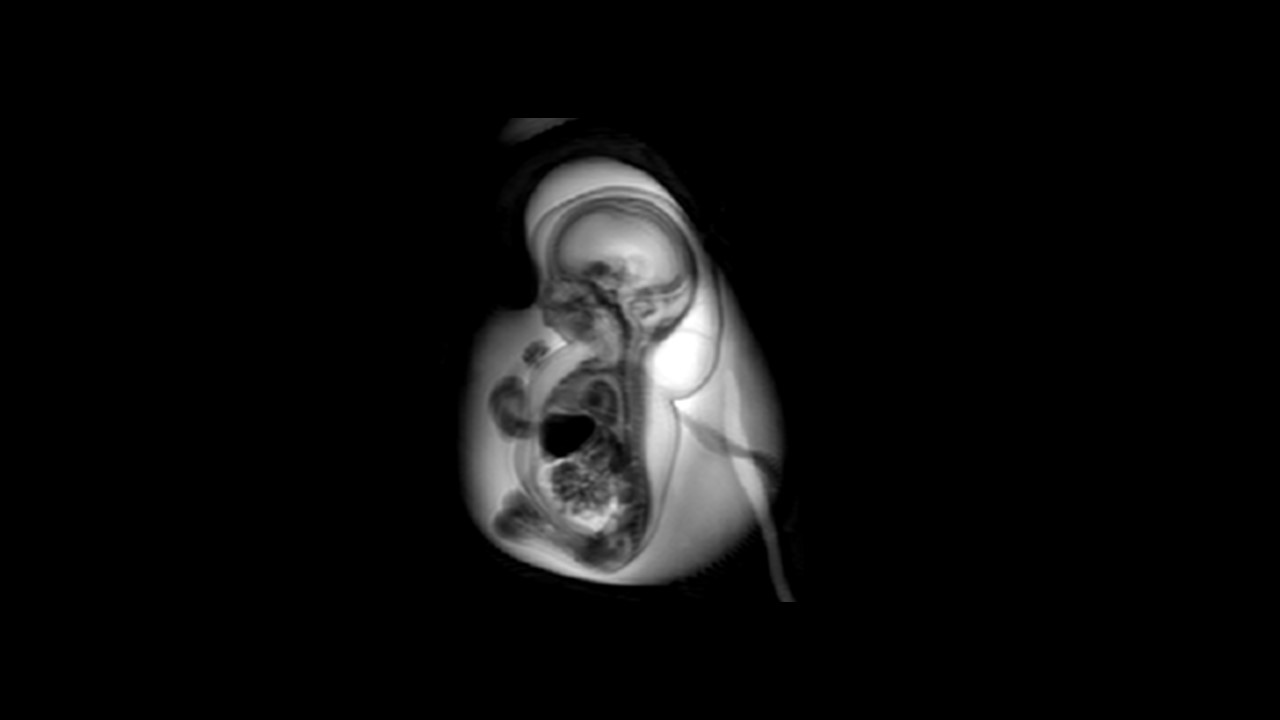

This online pediatric radiology course Fetal MRI From Head To Toe will provide participants with the knowledge to perform a conclusive fetal MRI examination. Also to know the steps of normal organ development at the respective gestational age and to be able to recognize deviations from normal organ development.